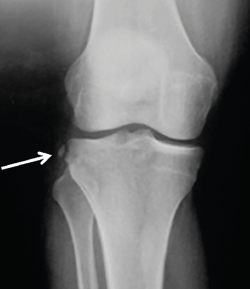

Figura 2. Radiografía anteroposterior de una rodilla derecha, donde puede apreciarse una fractura de Segond (flecha blanca).

- Radiografía (Rx): la imagen radiológica más característica que se relaciona con la lesión del LAL es la fractura de Segond, aunque esta solo está presente en un 1,25% de los pacientes con lesión de LCA(34)(Figura 2).

Se ha demostrado la correlación entre los hallazgos en ecografía y RM con alto grado de pivot shift en lesiones de LAL(36,40). Mediante esta exploración pueden detectarse tanto la lesión propiamente dicha del LAL, como la fractura de Segond y otros signos indirectos como la impactación del cóndilo femoral lateral (Figura 3).